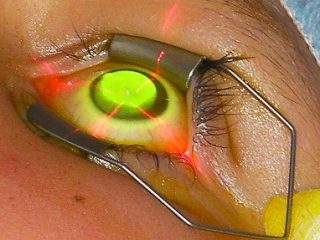

– Crosslinking corneano

O crosslinking é o único procedimento comprovadamente eficaz para interromper a progressão do ceratocone. Ele fortalece a estrutura da córnea por meio da aplicação de riboflavina (vitamina B2) ativada por luz ultravioleta A, promovendo a formação de novas ligações entre as fibras de colágeno corneano.

Isso aumenta a rigidez da córnea e impede que ela continue se deformando.

Esse é um procedimento realizado em centro cirúrgico, com anestesia tópica e ambiente estéril. Após o procedimento, o paciente usa uma lente de contato terapêutica por alguns dias, além de colírios antibióticos e anti-inflamatórios.

Pós-operatório do Crosslinking

Após o crosslinking, o paciente geralmente utiliza uma lente terapêutica por alguns dias para proteção da córnea. É comum sentir desconforto, sensibilidade à luz e lacrimejamento nas primeiras 48 a 72 horas. O repouso visual é essencial nesse período. O retorno gradual da visão ocorre ao longo de algumas semanas. O uso de colírios antibióticos e anti-inflamatórios é obrigatório, bem como os retornos para reavaliação.